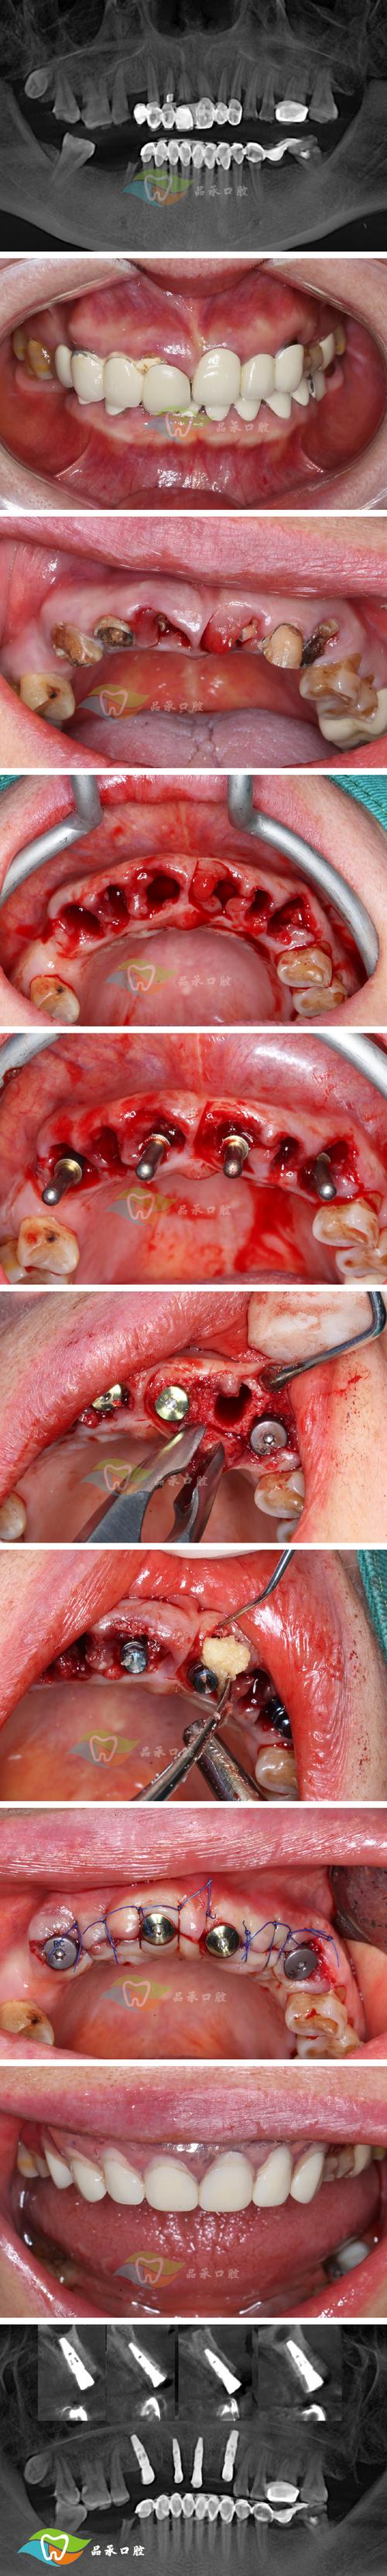

感染和骨坏死同样危险,手术需截开骨骼,若术中无菌操作不严格,或术后患者护理不当(如过早进食硬物、口腔卫生差),可能引发颌骨骨髓炎,严重时,坏死的骨块需被切除,导致面部塌陷,二次修复难度极大,正畸治疗过程中的“牙齿移动”也可能踩坑:为排齐牙齿,医生过度加力可能导致牙根吸收、牙齿松动,甚至脱落——曾有患者术后出现多颗牙牙根吸收超过1/3,最终不得不拔除种植,代价惨重。